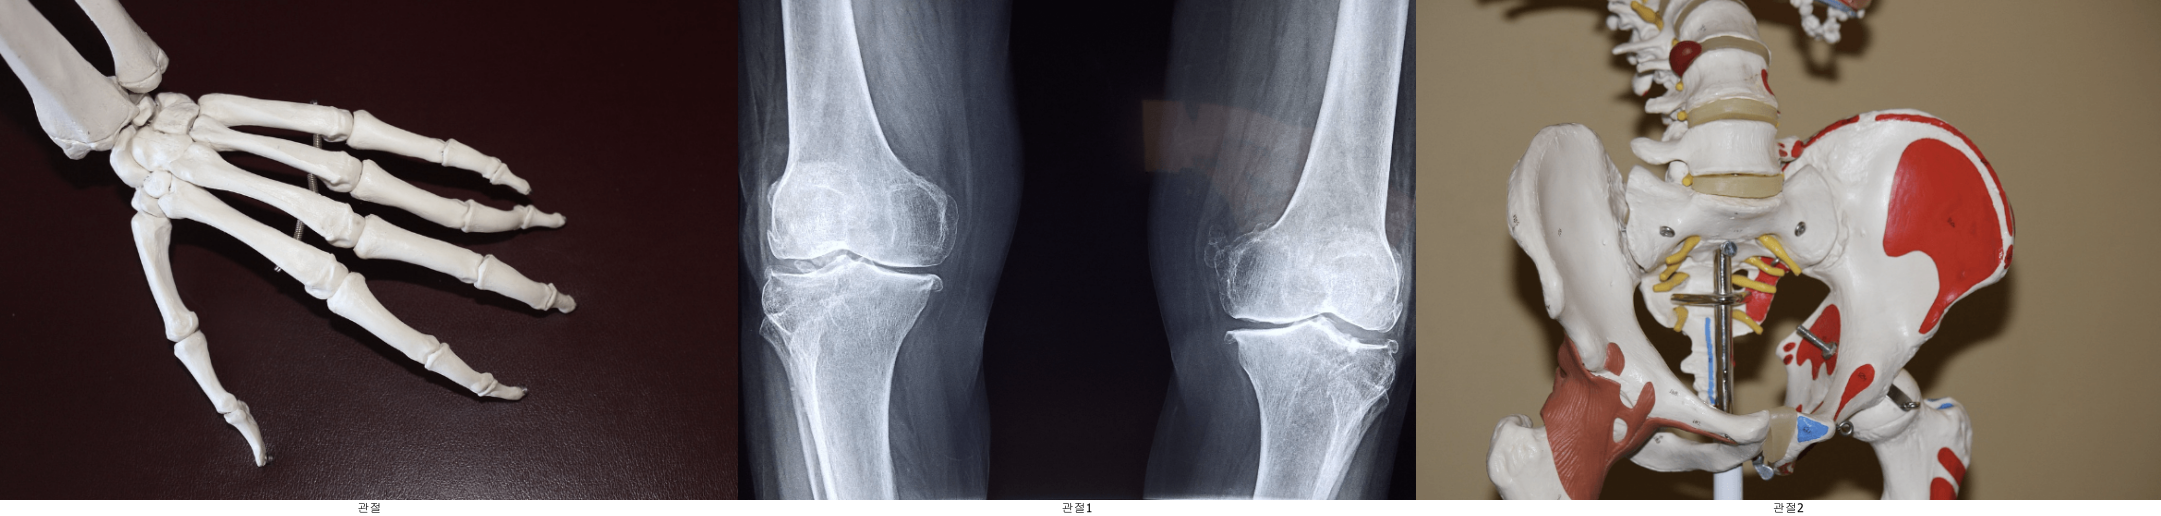

2) 관절 건강 지원

콜라겐은 관절과 연골의 주요 구성 요소입니다. 저분자 콜라겐 펩타이드는 관절의 염증을 줄이고, 연골을 보호하며, 통증을 완화하는 데 도움을 줍니다. 관절 건강이 걱정되는 분들에게 필수적인 보충제로 추천할 만합니다.